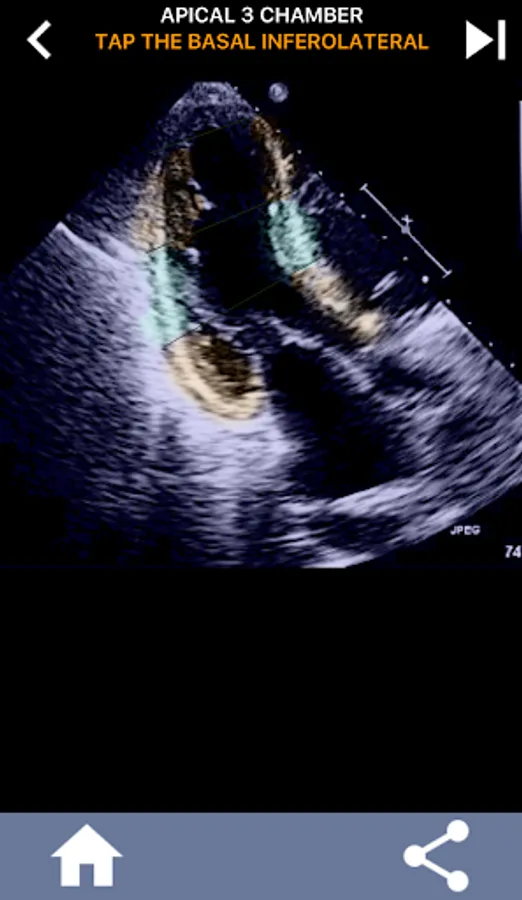

This app will test your knowlegde using actual echo images, which I often find to be the best teaching method.